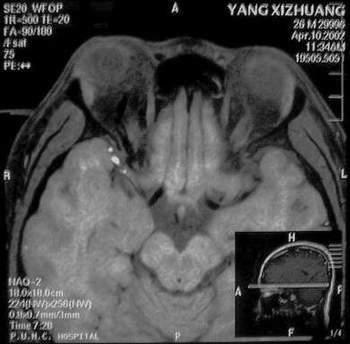

MRI及增强结果如下:

患者压颈及其它Valsava试验结果阴性。从MRI分析,在T1、T2、T+C检查该支血管均为明显流空现象,说明该血管血流速度很快,而从走行和分布看,眼上静脉可能性很大。也许也不能除外异常的眼动脉或异常血管。眶内主要可能的血管病变包括颈内动脉海绵窦瘘(高流窦)、AVM、眼眶静脉曲张、海绵状血管瘤、静脉性血管瘤、毛细血管瘤和眶内动脉瘤。。

1、颈内动脉海绵窦瘘:该患者临床有一部分支持该诊断。但从影像分析,海绵窦未见明显扩张;眼外肌未见明显充血扩张的长T1、长T2信号;颈内动脉海绵窦瘘常可见继发到血栓,可见到短T1、长T2的血栓信号。

2、眼眶静脉曲张:该疾患一般常见于小儿。该患大多数会出现Valsava试验阳性,间歇性突眼。不符合该患。影像学检查,于曲张静脉内常可见血栓和静脉石。所以不符合该患。

3、AVM:患者目前的影像学资料尚不全面,但可符合该诊断。临床上改病常见于30岁左右年轻人,单侧发病,于本患较符合。问题在于临床没有明确的血管杂音,似乎难以解释。

纵上所述:本人觉得,患者AVM可能性较大,同时不能除外眶内动脉瘤。